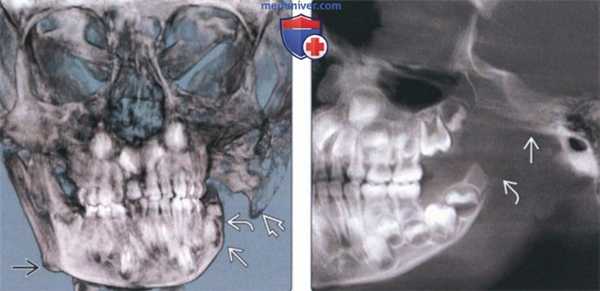

(Слева) На сагиттальной КЛКТ определяется посттравматическое расщепление правого мыщелка. Визуализируется наружная часть расщепленного мыщелка. Шейка мыщелка не визуализируется, имеет место задняя угловая деформация.

(Справа) На сагиттальной КЛКТ (более медиальный срез) у этого же пациента в передних отделах мыщелка визуализируется выбухающий участок неправильной формы. (Слева) На корональной КЛКТ у этого же пациента визуализируются наружная (меньшая) и внутренняя (большая) части мыщелка, разделенные V-образным вдавлением в центре. Внутренняя часть, вероятно, представляет собой оригинальный мыщелок, сросшийся с шейкой после перелома, и подвергшийся ремоделированию.

(Справа) На корональной КЛКТ левого ВНЧС визуализируется расщепленный мыщелок с умеренно глубоким и широким вдавлением в центре, разделяющим мыщелок на наружную (меньшую) и внутреннюю (большую) части. (Слева) На сагиттальной КЛКТ визуализируется расщепленный мыщелок слева с углублением в центре. Суставная ямка и суставное возвышение не изменены.

(Справа) На корональной КЛКТ у этого же пациента визуализируется углубление в центре мыщелка, широкое в передних отделах и узкое - в задних.